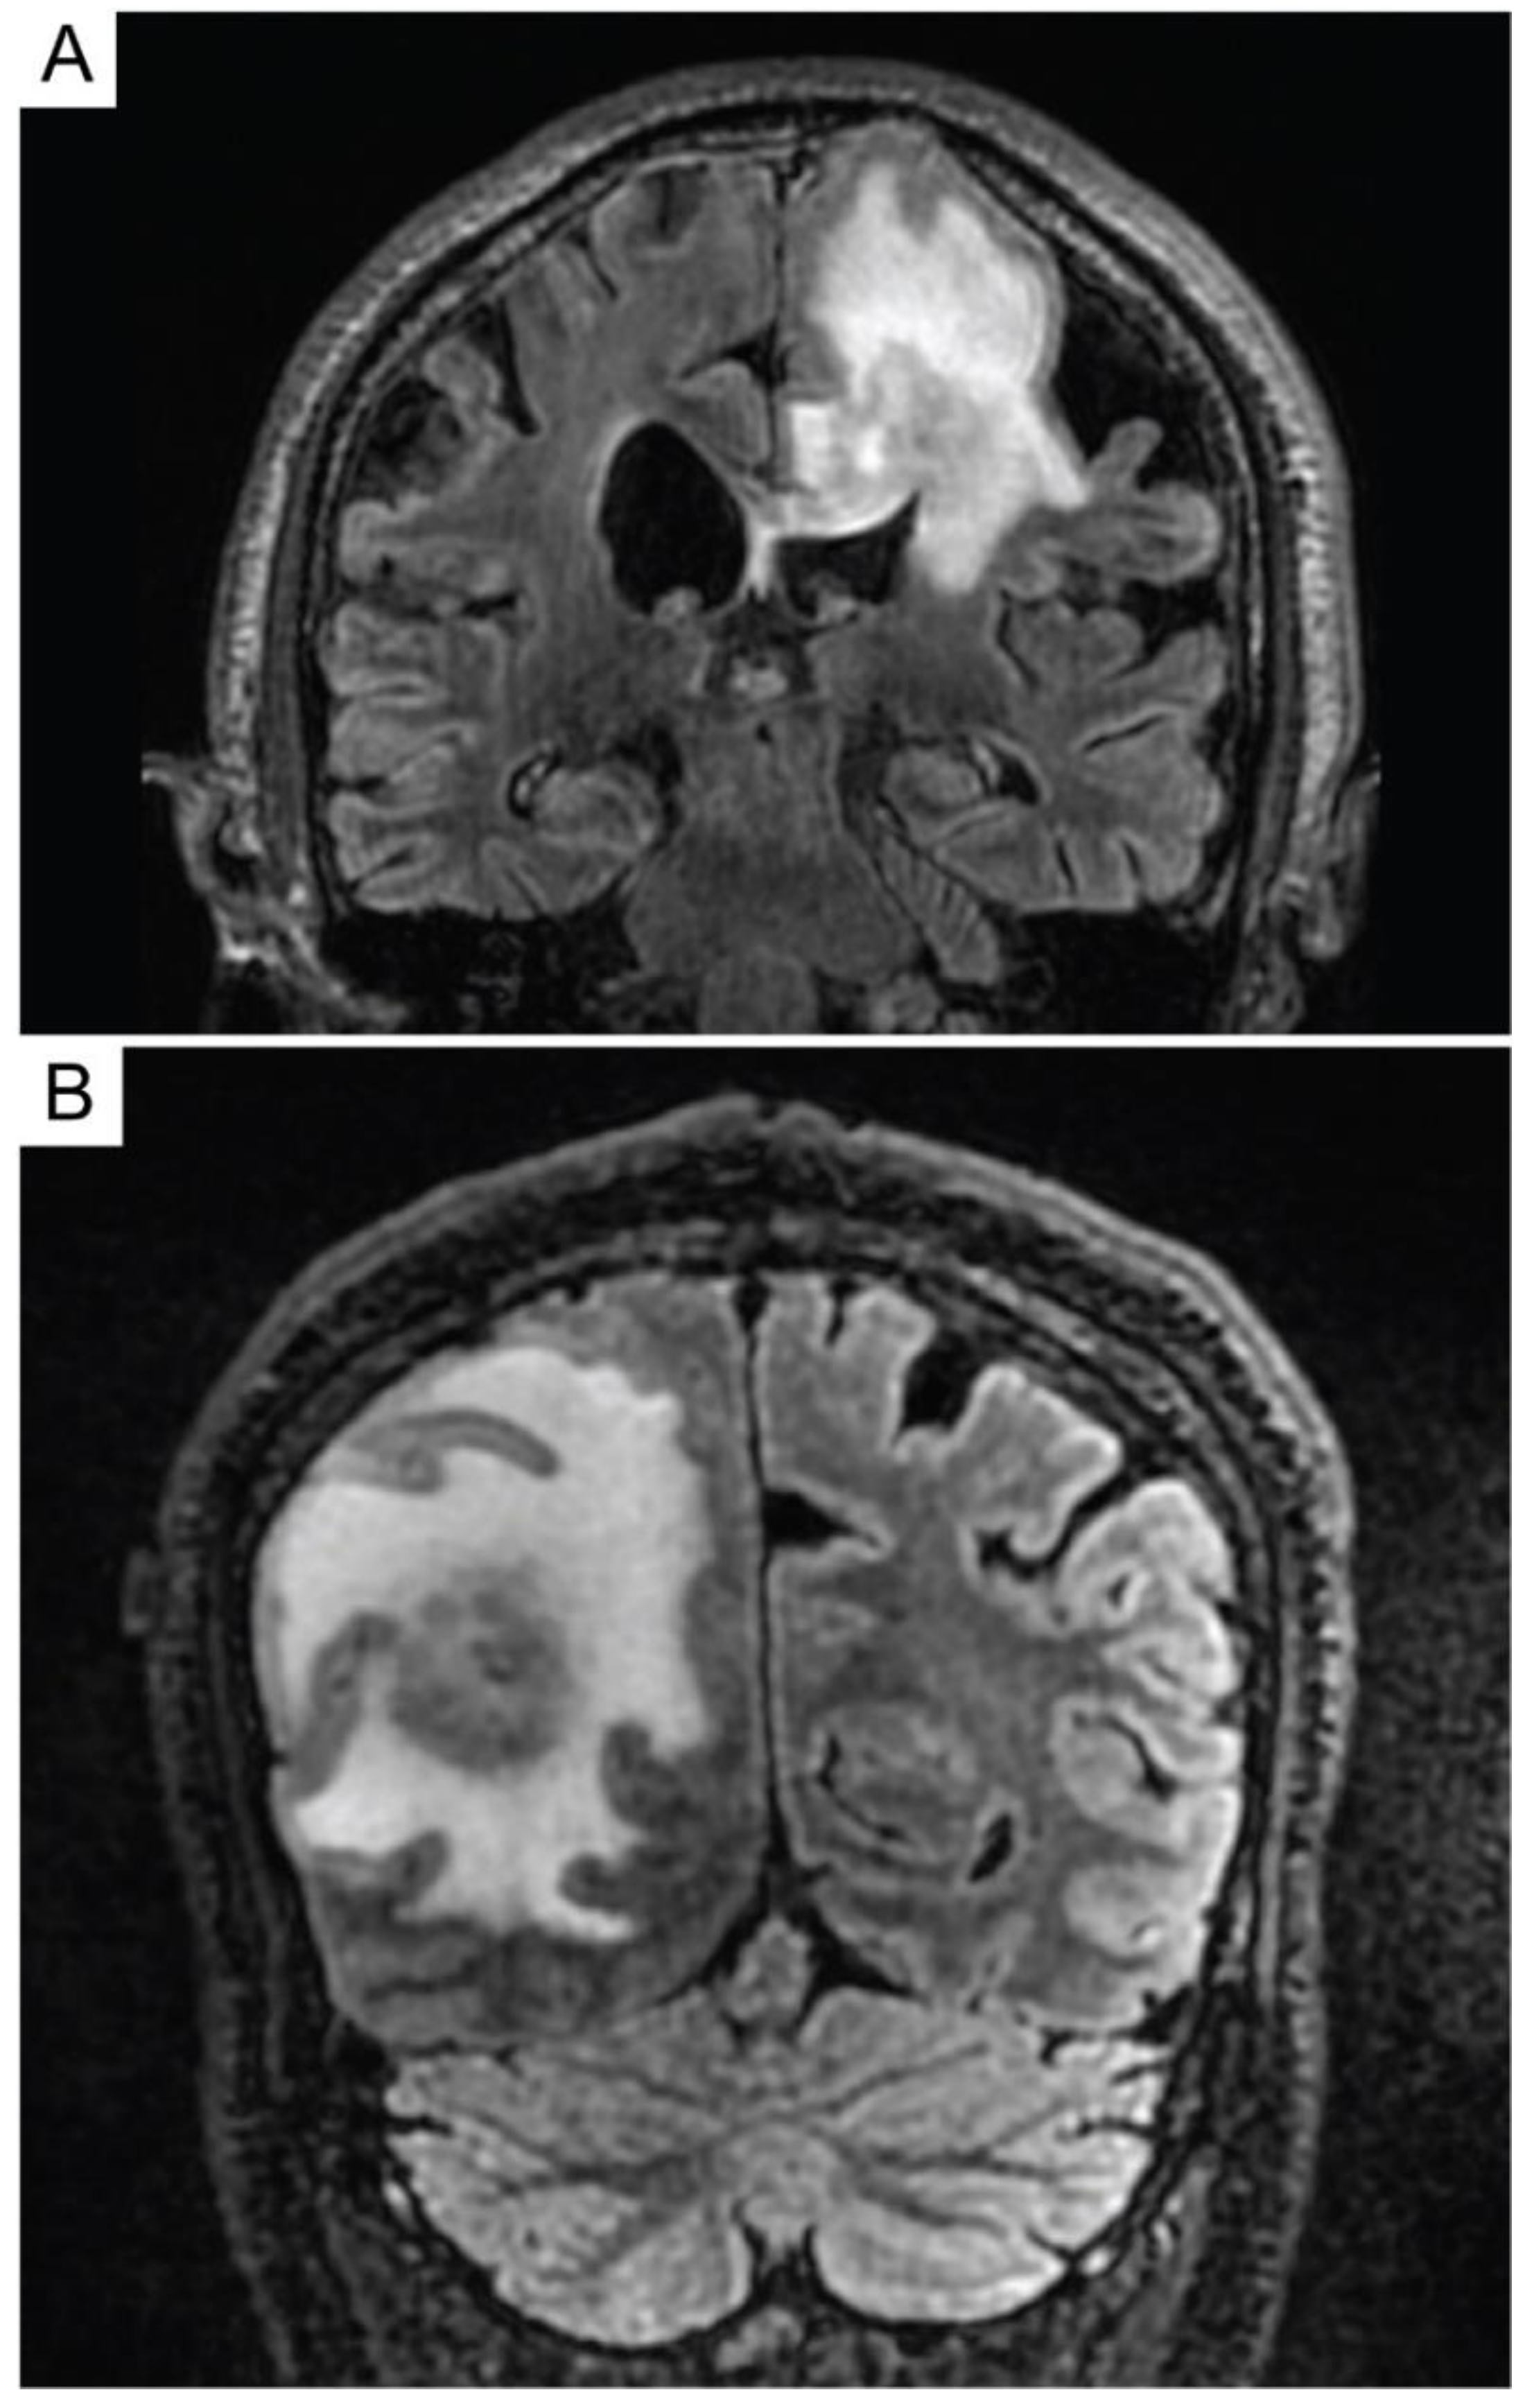

6. Primary Central Nervous System Diffuse Large B-Cell Lymphoma (PCNS DLBCL)